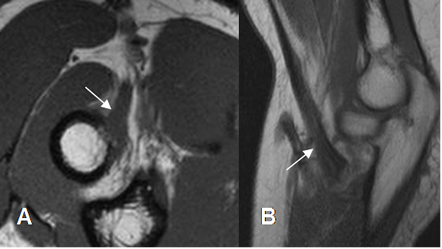

Fig 50. Tendinitis del bíceps.

A: RM vista axial en T1 y B: RM vista sagital en T1.

Aumento en la señal sobre la inserción del tendón, por tendinitis.